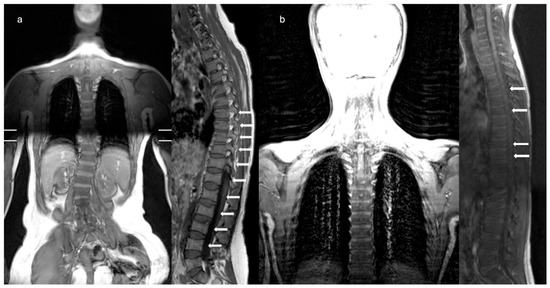

Hajdu–Cheney Syndrome in a Two-Generation Family: Longitudinal Skeletal Progression and Differential Therapeutic Responses in a Mother and Her Son

by Ruggero Lanzafame, Thomas Zoller, Angelo Pietrobelli, Giorgio Piacentini, Rossella Gaudino, Alessandra Guzzo, Giovanni Adami, Francesco Pollastri and Franco Antoniazzi

Hajdu–Cheney syndrome (HCS) is a rare genetic skeletal disorder caused by truncating variants of NOTCH2, characterized by progressive bone resorption and marked phenotypic heterogeneity. Despite advances in understanding Notch signaling in skeletal biology, longitudinal clinical data tracking disease evolution from early childhood through adolescence are lacking. Here, we report a rare longitudinal intrafamilial observation of HCS in a mother and her son carrying the same NOTCH2 pathogenic variant, providing novel insights into disease evolution and therapeutic response. Over extended follow-up, the son exhibited early vertebral fragility despite preserved or supranormal bone mineral density (BMD), whereas the mother developed severe osteoporosis, progressive acro-osteolysis, and multiple vertebral fractures. Longitudinal analysis revealed a dissociation between vertebral fragility and densitometric decline, challenging the paradigm that low BMD is the primary driver of skeletal morbidity in HCS. Treatment responses differed between the two patients, with bisphosphonate therapy in the son associated with stabilized BMD without altering vertebral structural progression, and denosumab in the mother associated with increased BMD, but not preventing progression of acro-osteolysis. Additionally, the emergence of extra-skeletal features during adolescence expands the phenotypic spectrum of HCS and suggests previously unrecognized systemic involvement. These data highlight intrinsic limitations of current therapeutic strategies and emphasize the need for targeted interventions addressing sustained Notch2 activation. Our findings contribute to the understanding of the natural history and therapeutic challenges of HCS, providing the framework for future mechanistic and translational research. Full article

Figure 1